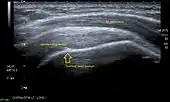

![]() Longitudinal ultra sonography of the supraspinatus tendon |